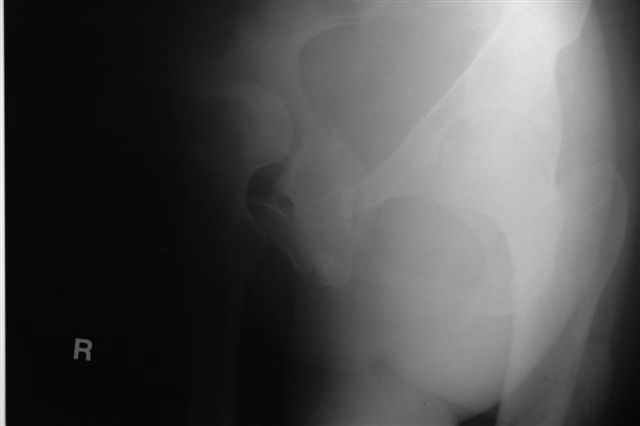

Трудности возникли сразу после рассечения большой ягодичной мыцы - короткие наружные ротаторы едва ли определялись - головка и шейка (как видно на

снимке) ушли в таз, пришлось воспользоваться дистрактором( ручные попытки выдернуть голову из под проксимального фрагмента - безуспешны) Шарнирный дистрактор - великое изобретение, без него репозиция была просто невозможна.

> наружные ротаторы едва ли определялись - головка и шейка

> ( как видно на

> снимке) ушли в таз, пришлось воспользоваться дистрактором

P.S. в приложении R пациентки с похожей проблемой доступа.. за исключением того, что перелом

двухколонный. Вертлугу лечили Y доступом.